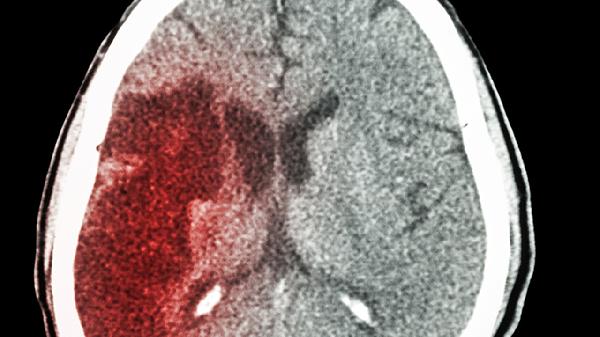

凌晨三点,救护车刺耳的鸣笛声划破夜空,50岁的张先生被紧急送医时已经言语不清——CT显示大面积脑梗,虽经全力抢.救仍不幸离世。主治医生翻开他的体检报告:“血液黏稠度超标3倍”的警.示赫然在目,而罪魁祸首竟是每周必吃的红烧肉。